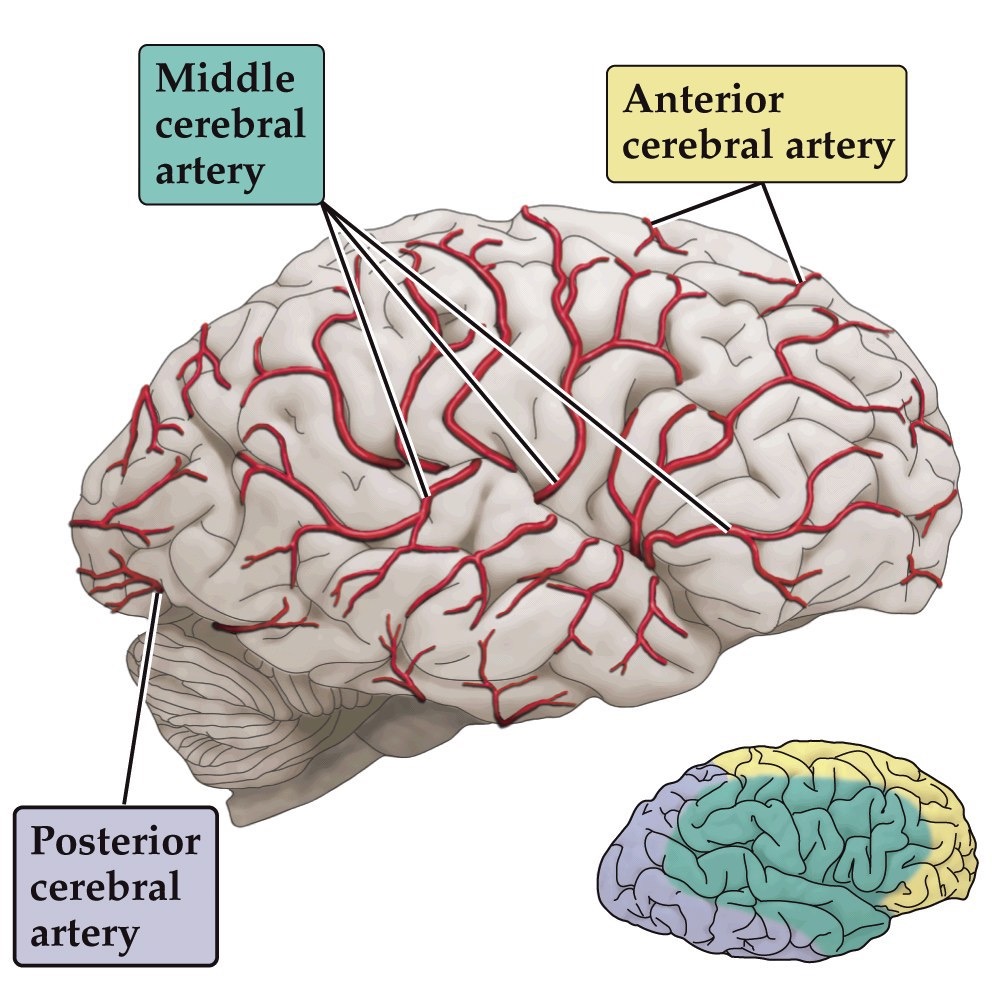

Cerebral circulation